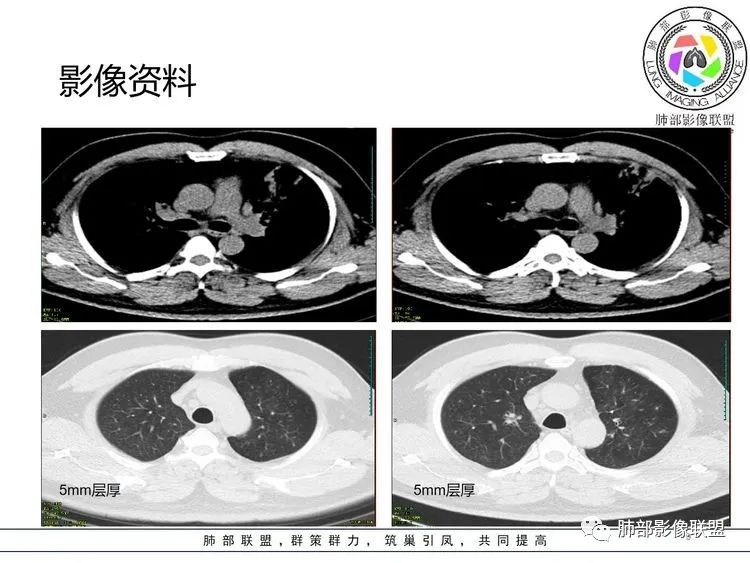

张延军: 左肺上叶前段沿支气管束周围见实变影,边缘收缩,界不清,内见小空洞影,与支气管相通,病变周围散在结节及斑片状高密度影,树芽征(+),中年男性,类似结核中毒症状,感染指标升高,考虑NTM,结核代排。

joyzhy:中年男性,咳嗽咳痰,炎性指标升高。影像,左肺上叶片状实变,部分平直,部分内收,支气管血管束增厚,头孢类治疗后效果不佳。考虑非典型肺炎,支原体?鉴别:吸入性肺炎

若晗:左肺上叶空洞伴树芽!结合临床及发病部位,考虑NTM可能性大,鉴别奴卡

衡妈: 实变+支气管充气征,可见支气管壁增厚,病灶边缘模糊磨玻璃。我没有看到树芽;NTM 一般要有背景 比如支扩

张丽红: 有发热,咳嗽呼吸道感染症状。左肺上叶斑片影,内部支气管走行自然。右肺也有散在斑片影。考虑非结核分枝杆菌,结核

良孑:实变,虫蚀样空洞,树芽,还是首选TB

采莲: 中年男性,咳嗽咳痰伴发热10天,血象CRP升高,血沉快,但白细胞及中性粒细胞比例没有明显升高,左肺上叶斑片实变影,支气管通而不畅,考虑肺炎、肺结核可能性大,但是肺泡灌洗液Xpert阴性,t-spot阴性,肺结核可能性就小了,不排除NTM,但是NTM在上叶的不多见。实在想不出来,血象不高,支原体肺炎真有可能。